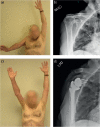

Since the introduction of reverse total shoulder arthroplasty (RTSA) in 1987 (in Europe) and 2004 (in the United States), the number of RTSAs performed annually has increased.Although the main indication for RTSA has been rotator cuff tears, indications have expanded to include several shoulder conditions, many of which involve dysfunction of the rotator cuff.RTSA complications have been reported to affect 19% to 68% of patients and include acromial fracture, haematoma, infection, instability, mechanical baseplate failure, neurological injury, periprosthetic fracture and scapular notching.Current controversies in RTSA include optimal baseplate positioning, humeral neck-shaft angle (135° versus 155°), glenosphere placement (medial, lateral or bony increased offset RTSA) and subscapularis repair.Improvements in prosthesis design, surgeon experience and clinical results will need to occur to optimize this treatment for many shoulder conditions. Cite this article: EFORT Open Rev 2018;3:58-69 DOI: 10.1302/2058-5241.3.170044.